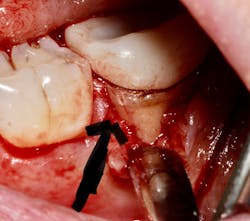

The periodontium surrounding the tooth can be a source of pain, especially if there is a concurrent periodontal lesion along with an endodontic lesion (figure 3). The tooth should be clinically examined and radiographs taken following root canal treatment to evaluate both hard and soft tissue. Hard-tissue defects, such as intrabony defects and furcation involvement, can cause inflammation leading to tooth pain. In addition, soft-tissue recession can expose root surfaces, which can then lead to sensitivity and tooth pain. Food impaction, especially if the tooth is temporized, can also mimic tooth pain. Gingival irritation from the rubber dam clamp used during the root canal can simulate tooth pain, but it is usually temporary and can be alleviated with rinses or medicaments. Referral to a periodontist may be required for pain of periodontal origin.